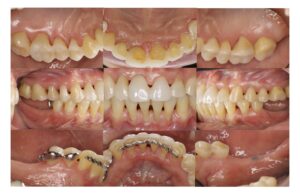

治療前 下顎両側大臼歯欠損は放置され、上下顎前歯は前方に傾斜・突出した状態であり、上顎の右側中切歯は動揺が著明で、全顎的に歯肉の発赤・腫脹がありました。

治療後 上下顎両側大臼歯欠損は目立たない部分入れ歯が装着され、上下顎前歯の前方への傾斜・突出と隙間の改善を認めます。、全顎的な歯肉の発赤・腫脹も改善されています。

3. 下顎部分入れ歯を装着しながらの歯列矯正処置

歯周病患者さんであるため、ワイヤーを用いた歯列矯正処置(マウスピース矯正では歯が揺れてしまうため)を9ヶ月行い、歯の病的な位置異常を是正して、見た目とともに機能の改善を図りました。部分入れ歯の設計を考慮して歯列矯正処置を行うとともに、奥歯での噛み合わせを確保しています。

4. メインテナンスへ移行

歯列矯正処置の後、最終的な歯の修復処置(ダイレクトボンディング)を行い、メインテナンスへ移行しました.早期に製作した部分入れ歯は今後も使用していきます。初診時と比較して、歯肉の炎症を認めず、出血点はほぼ消失し、歯の周りの歯槽骨梁の改善が認められました。